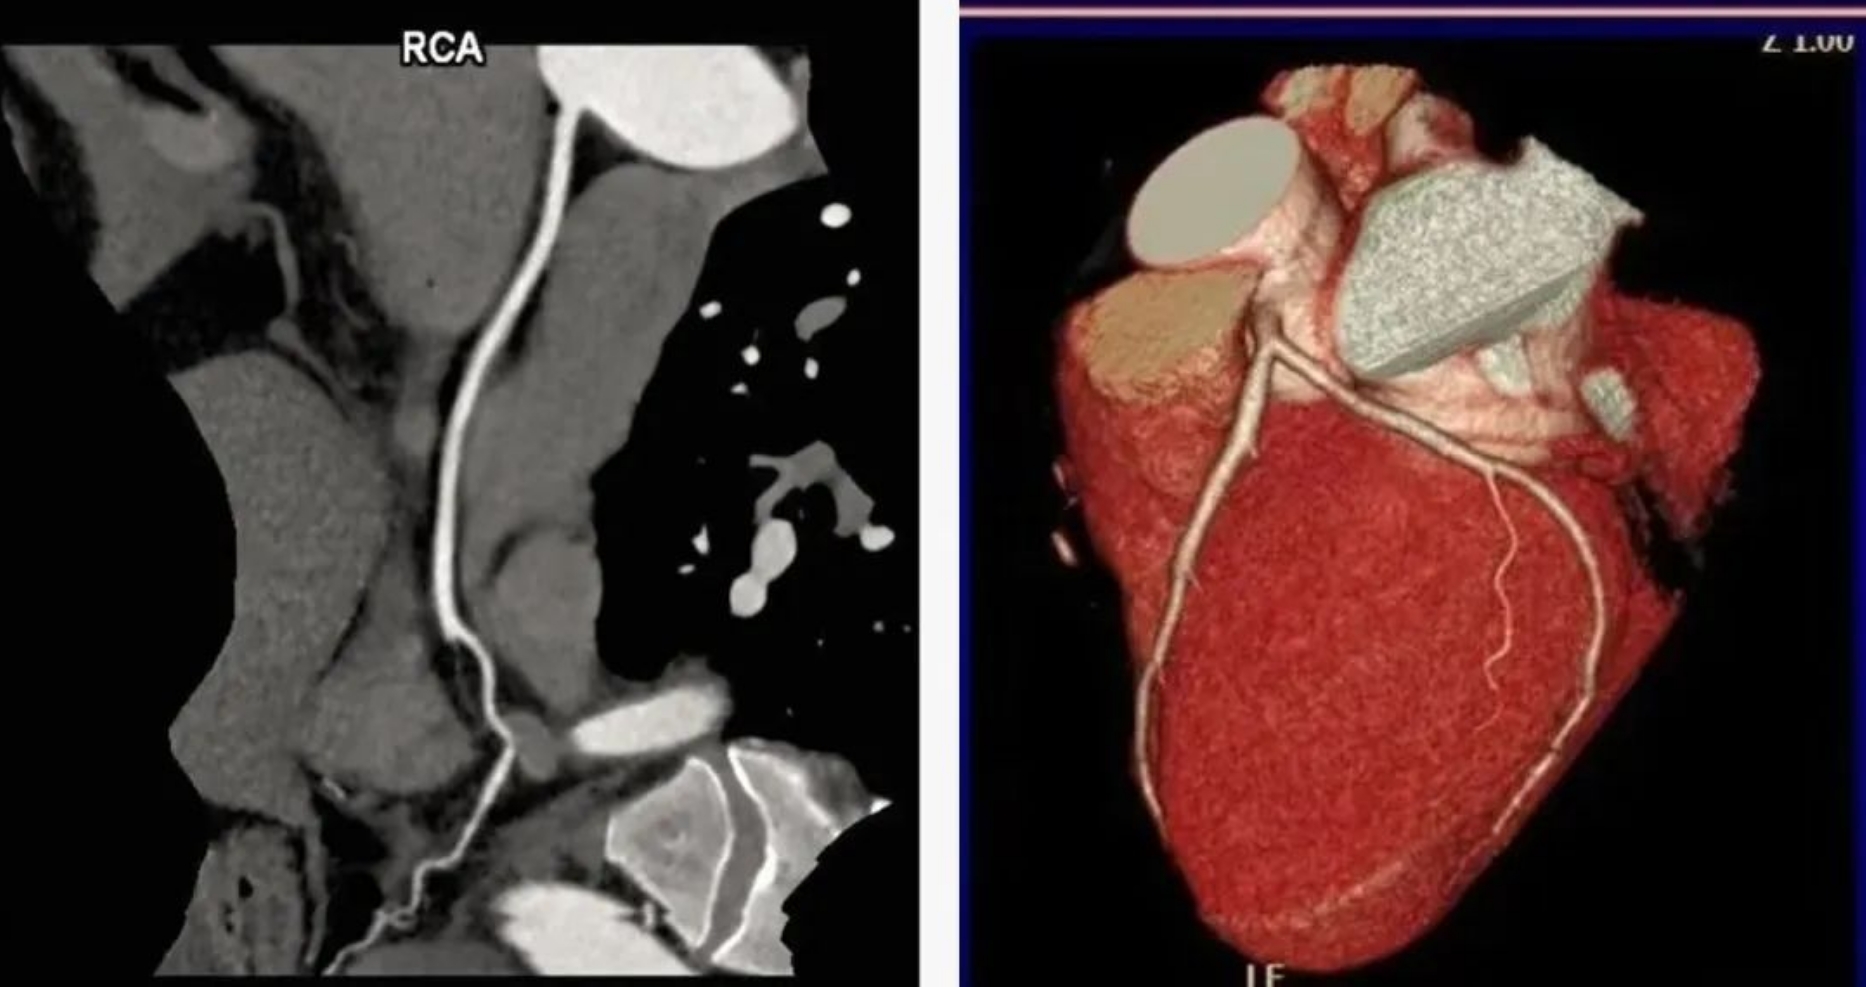

本次引進(jìn)的全新64排128層人工智能螺旋CT具有檢查更加精細(xì)、圖像更加清晰、掃描速度快和輻射劑量小等多種優(yōu)點(diǎn)。除了可進(jìn)行常規(guī)CT檢查、普通增強(qiáng)CT檢查外,還可對(duì)全身大血管、腦血管、心臟血管進(jìn)行檢查;強(qiáng)大的三維重建功能可發(fā)現(xiàn)普通DR、常規(guī)CT所難確診的病變。

用該設(shè)備做心血管系統(tǒng)檢查,能得到對(duì)比度極佳的血管圖像。大大提高了診療的精準(zhǔn)度及工作效率,有利于醫(yī)生及早發(fā)現(xiàn)微小病灶。

通過該新型CT,不僅年老體弱的病人可以接受CT冠脈造影檢查,得到的CT圖片質(zhì)量也非常清晰,對(duì)臨床診斷的價(jià)值更大。